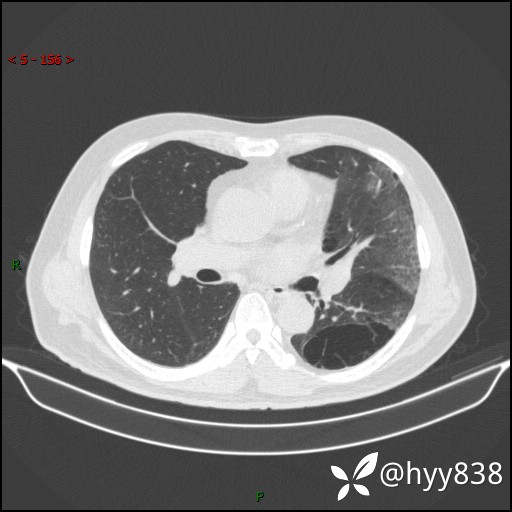

一周后胸部CT